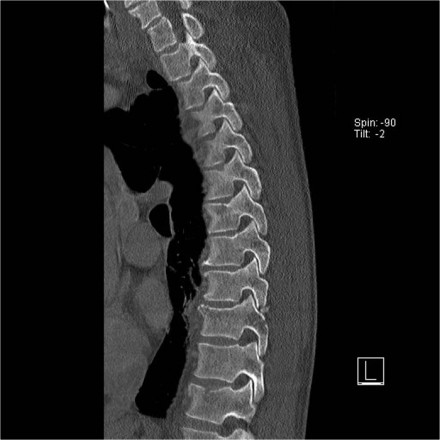

The images show a compression fracture.

All we see is a cortical disruption in the upper anterior wall of the vertebral body and slight loss of height ventrally.

The posterior vertebral cortex is intact.

The sagittal reformatted image also shows the cortical disruption.

Notice that on a 2.5mm axial slice you can miss these fractures.

You have to look at the thin slices to detect such a subtle fracture.